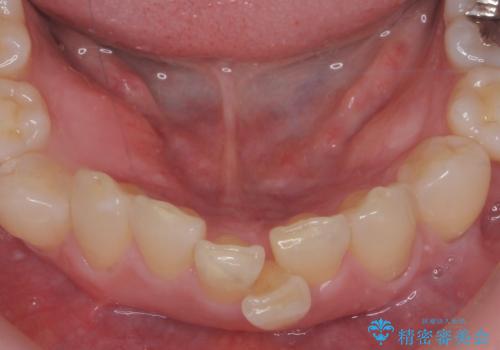

インビザラインで行う前歯のみの部分矯正

- 長年気になっていた前歯の歯並びを改善したいと、矯正治療を希望され思い切って来院されました。

費用と期間を相談し、「気になっているのは前歯だけ。」とのことでしたので前歯のがたつきのみをインビザラインで改善する矯正治療の計画を立てます。

しっかりとマウスピースの装用時間を守っていただき、非常にスムーズに治療を終了することができました。